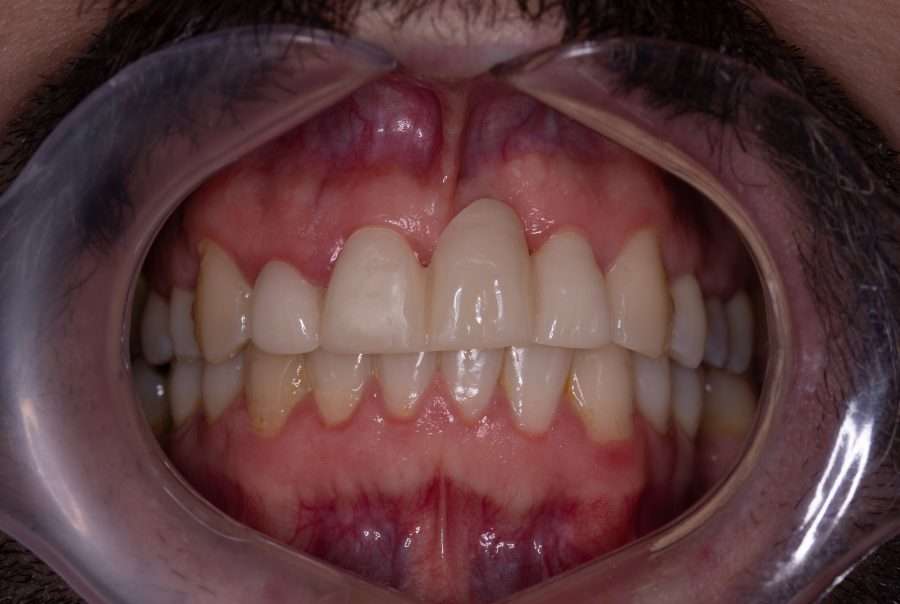

We created a dental bridge and a full ceramic veneer to restore the entire incisor group, achieving symmetry and harmony from all perspectives. Since there is no visible exposure in the smile, the gingival margin line and its modifications are not aesthetically disruptive.

We chose an exclusively prosthetic approach in this case of replacing a previously lost central incisor, with a history of trauma, multiple endodontic retreatments, significant mobility and substantial bone tissue loss.